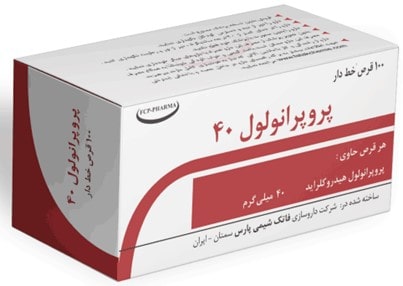

پیشگیری از خونریزی